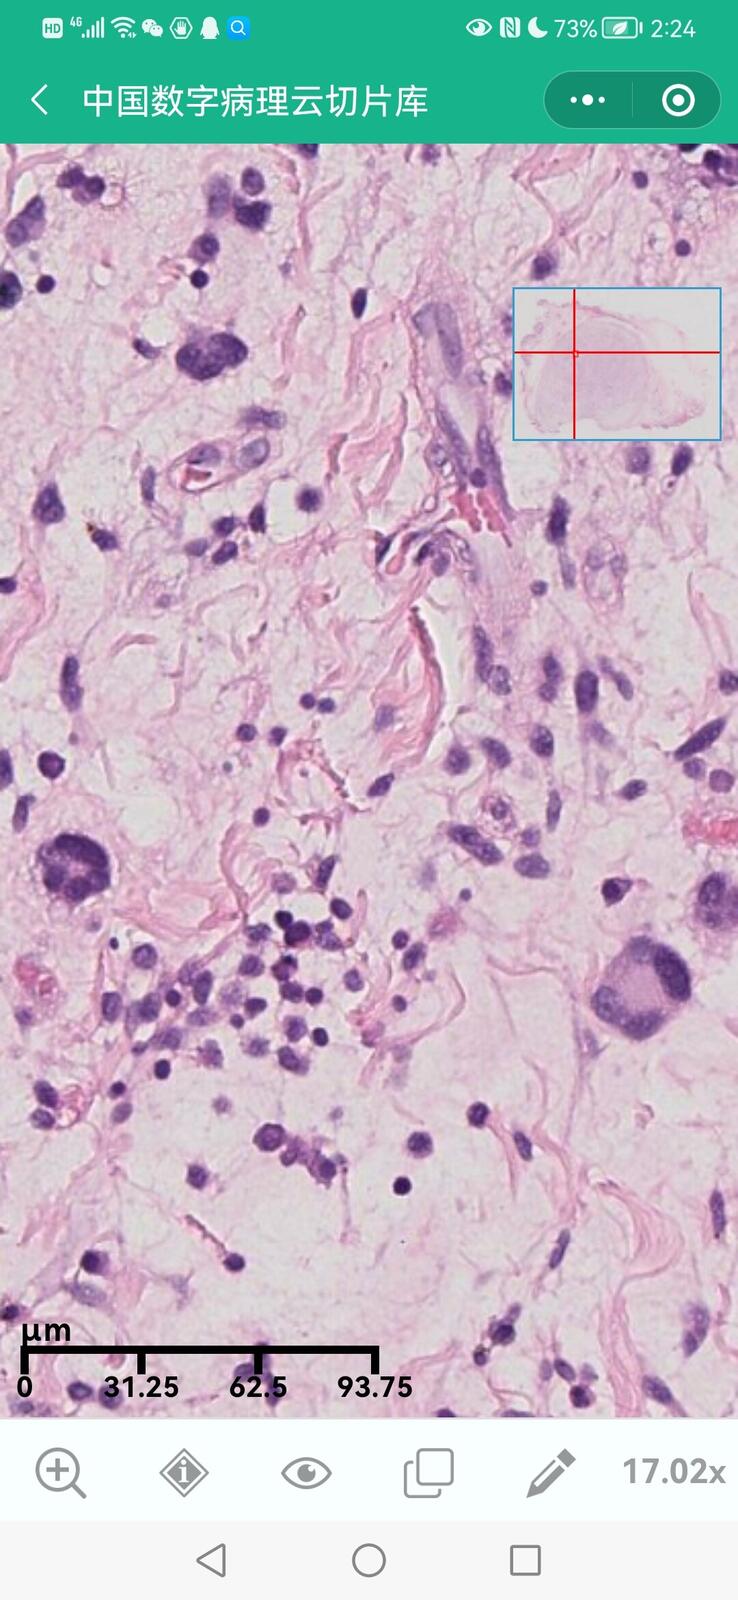

乳腺多形性脂肪肉瘤